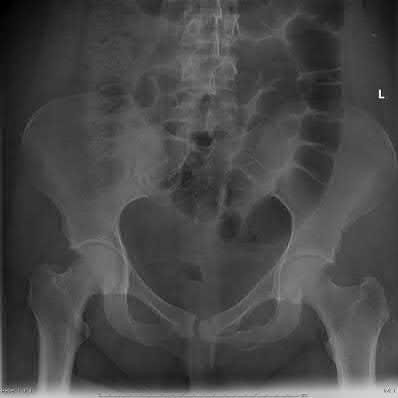

A 34-year-old male presents with the right posterior wall acetabular fracture shown in Figure A. What is the most accurate method to test for hip stability in this patient?

Dynamic fluoroscopic examination of the affected hip under anesthesia is considered the best method of predicting hip stability. Fragment size, which can be calculated using the Keith, Moed, or Calkins method, can be used to predict hip stability radiographically, however they are not as accurate. In general it is thought that posterior wall fractures involving less than 20% of the posterior wall are stable, whereas those involving greater than 40%-50% are unstable. Unfortunately, this leaves an indeterminent zone (20-40%) which does not provide guidance in treatment.

Moed et al retrospectively reviewed 33 patients with posterior wall fractures who underwent dynamic fluoroscopic stress testing and compared the results of this testing to the Moed, Calkins, and Keith method of hip stability prediction. They found that the Moed method is the only reliable technique that is predictive of hip stability for small fracture fragments while also being predictive of instability for large fracture fragments. However, they also stated that there remain a substantial number of fractures involving 20% or more of the posterior wall that are both stable and unstable by examination under anesthesia. Therefore, they recommend dynamic fluoroscopic examination for assessment of hip stability in the presence of a posterior wall fracture.

Moed et al in their second paper reviewed all patients with less than a ≤50% of the acetabular wall fracture, adequate imaging, and documented EUA results.

The group looked at multiple variables including fracture fragment size,

superior exit point of the fracture, center-edge angle, acetabular index, Tönnis angle, lateralized head sign, crossover sign, posterior wall sign, ischial spine sign, and hip version. Their conclusion was that no one variable was able to predict stability or instability and they continue to recommend EUA.

Tornetta et al conducted a study in which dynamic fluoroscopic stress views were taken of 41 acetabular fractures that met the criteria for non-operative management to determine subtle signs of instability. Of the 41 fractures, 38 were found to be stable and 91% of these had good or excellent outcomes at

2.7 years. They concluded that dynamic stress views can identify subtle instability in patients who would normally be considered for non-operative treatment.